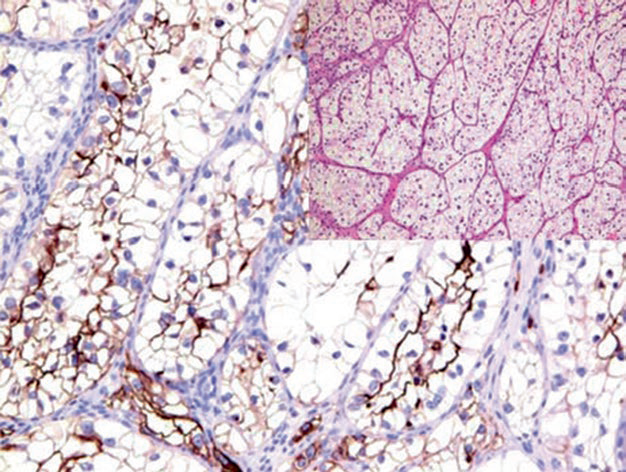

图2. 胚胎12周的肾脏,Pax-8在肾脏集合系统及肾盂处尿路上皮阳性表达。